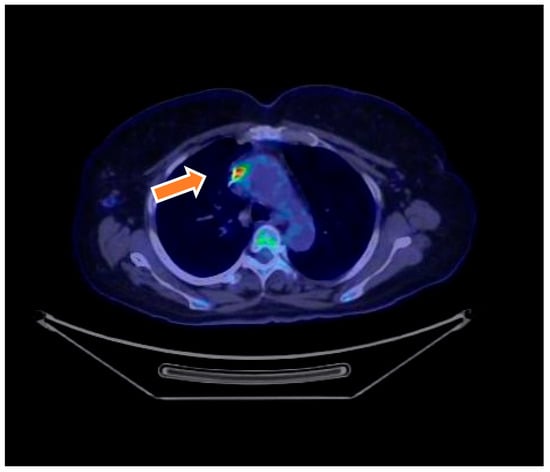

18F-FDG PET/CT imaging played a crucial role in the diagnostic evaluation of patients with suspected infective endocarditis (IE). Among the 46 patients initially classified as having possible IE, PET/CT findings contributed to reclassification in 13 cases: 6 patients were reclassified as having definite IE due to positive radiotracer uptake localized around prosthetic valves or cardiac devices, fulfilling major imaging criteria according to the modified Duke criteria. Conversely, 7 patients were reclassified as having rejected IE following negative PET/CT findings, indicative of the absence of infection. Additionally, one patient initially classified as having rejected IE was reclassified as having possible IE based on new PET/CT findings suggestive of infection (Figure 2). Overall, 18F-FDG PET/CT demonstrated a sensitivity of 83.3%, specificity of 93.7%, positive predictive value (PPV) of 83.3%, and negative predictive value (NPV) of 93.7%. Upon exclusion of patients with suspected native valve endocarditis (NVE), diagnostic accuracy improved, with a sensitivity of 94.1%, specificity of 95.7%, PPV of 88.9%, and NPV of 97.7%. PET/CT was particularly valuable in cases with ambiguous echocardiographic and clinical findings, confirming definite endocarditis in 18 patients by detecting focal metabolic activity consistent with active infection. Moreover, PET/CT identified extracardiac infectious foci, including vertebral osteomyelitis and splenic emboli, in four patients, supporting a systemic infectious process. The integration of PET/CT findings with clinical and microbiological data enhanced diagnostic confidence and informed subsequent management strategies.

Figure 2. Transverse and coronal 18F-FDG PET/CT images show an infected prosthetic mitral valve. Culture after valve removal was positive for Staphylococcus aureus. 18F-FDG PET/CT image demonstrating abnormal metabolic activity around a prosthetic mitral valve lead and adjacent valve in a 75-year-old female. The PET/CT findings defined the presence of device-related infection and contributed to the classification of definite endocarditis.